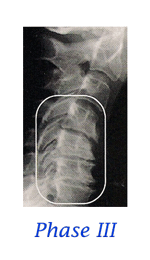

Stages of Spinal Degeneration

When it comes to the spine, the average person’s only interest is with PAIN. Statistics claim that each of us will be disabled with low back pain at least twice in our lives. We may, on average, only miss a couple days work, but many people find back pain to be a lifelong “challenge”. For too long, and too often, the general public has been coerced into thinking that surgery is the only answer for a diagnosis of “slipped disc”. But what is a “slipped disc”? Most people think it is like biting into a tuna sandwich and having all the tuna go out the backside. Oops! That must be really bad! Then again, you may have been told that your diagnosis is a “bulged disc”, “protruding disc”, “herniated disc”, “degenerating disc”, “Fragmenting disc” or maybe “degenerative disc disease”. How confusing can these disc problems be? VERY CONFUSING! . . . continue with Do You Have a "Slipped Disc"?